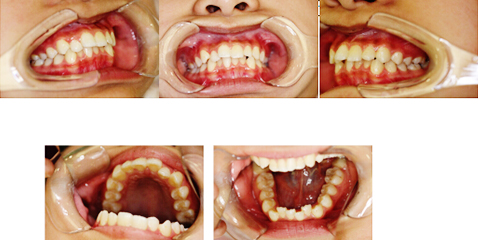

正畸治疗还要把握时机,有一些牙颌畸形如“地包天”、咬唇、吮指等不良习惯引起的畸形,要在三到五岁就进行治疗,越早治疗越好。一般的牙颌畸形在恒牙已经开始萌出时,也就是八到十岁时侯到正畸医生处做咨询、检查以便决定。青春快速生长发育期(一般女孩11~13岁,男孩12~14)时,牙齿替换完毕,颌骨仍有发育潜力,此时是进行固定矫治的最佳时期,绝大多数错颌畸形均可在此时解决。矫正之前医生会进行详细的口腔检查,拍X光,取分析模型,进行全面的综合分析,再得出正确的诊断和治疗计划,一般需要治疗一至两年,然后转入保持期。一些严重的骨性错颌,矫正后可能达不到理想的效果或因异常的生长型导致复发,需在成年后进行正颌外科手术矫正。

根据矫治器的不同,儿童正畸的常规方法可以分以下几类: